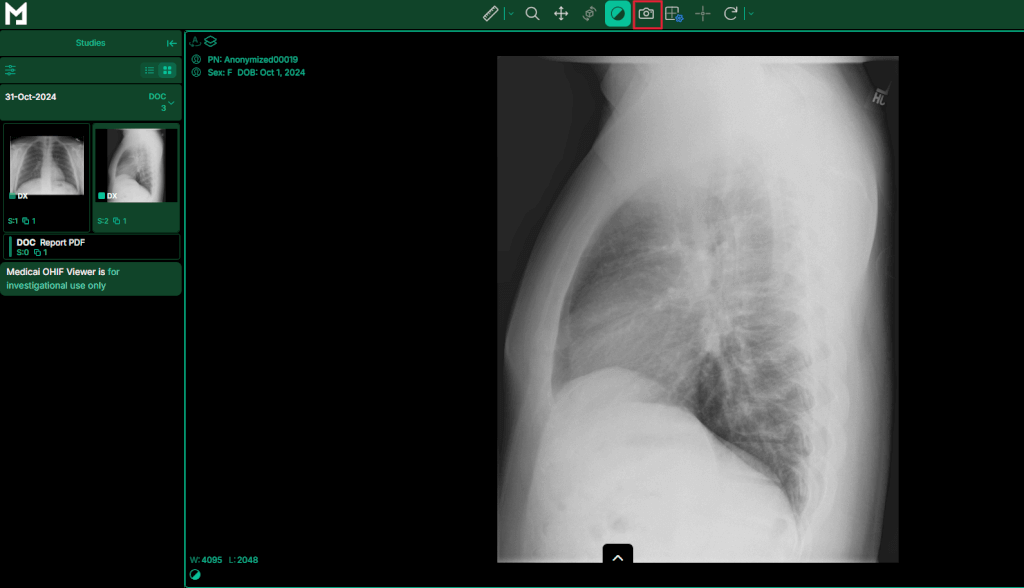

GUI Tools: Medicai DICOM Viewer

Graphical apps like Medicai DICOM Viewer let you load a DICOM series, select JPEG as the output format, and save instantly. These tools are ideal for quick, one-off conversions without writing any code.

- Open Medicai DICOM Viewer: Launch a GUI application like our DICOM viewer.

- Import the Study Folder: Use the “Upload File” menu to load the .dcm files either from a CD or your computer.

- Select Export Format: Navigate to the “Capture (Camera Icon)” dialog, choose “JPEG” as the output type.

- Export: Click “Save” then choose an output directory. The tool will convert the loaded file.